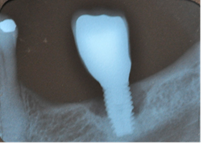

Question No. 2.- How to diagnose: Mucositis and Peri-implantitis? The term “peri-implantitis” was introduced by Mombelli in 19871, and then modified in the 1st European Workshop on Periodontology, to describe an inflammatory disease that leads to bone loss around dental implants2. Peri-implant diseases include: mucositis, described as an inflammatory lesion in the mucosa surrounding the implant, without concomitant bone loss3. The literature presents discrepancies regarding the clinical parameters to consider (Figure 1).

Early: Probing depth >4 mm, with bleeding and/or suppuration in >2 implant sites, and bone loss <25% of the total implant length (Fig. 2)